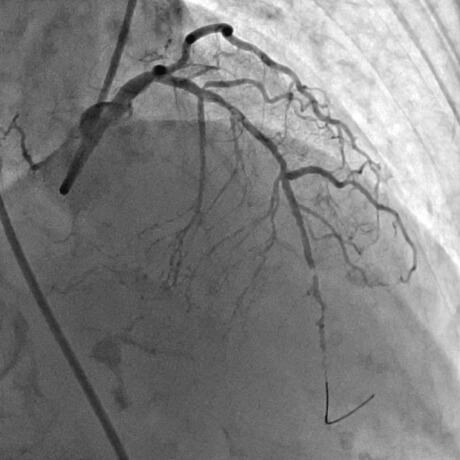

急性心筋梗塞症例へのPCI施行時の冠動脈造影画像

治療後最終の造影